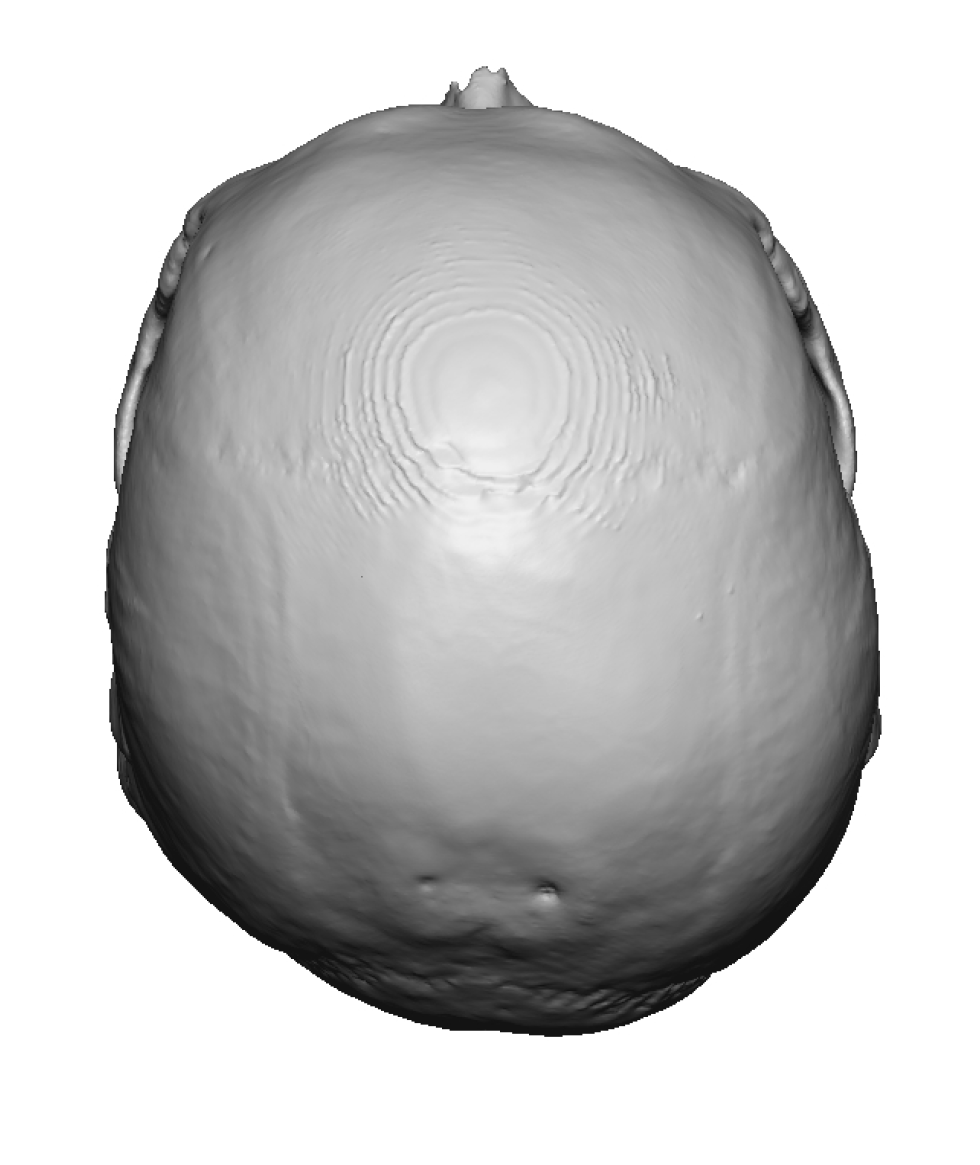

Patient 11

Desire to build out the back of his head which had bothered him his whole life.

Two-stage skull augmentation of the back of the head using a custom skull implant as the second stage. (first stage scalp expansion)

Desire to build out the back of his head which had bothered him his whole life.

Two-stage skull augmentation of the back of the head using a custom skull implant as the second stage. (first stage scalp expansion)